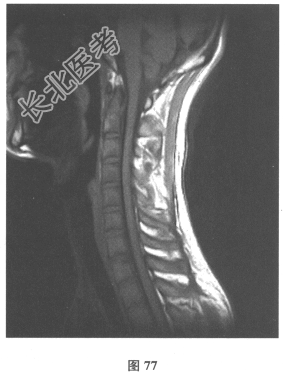

颅脑MRI:无异常。血清AQP-4抗体(-),脑脊液OB(+),各种自身抗体测定均阴性。VEP:右眼P100潜伏期延长。患者3年前无明显诱因出现双下肢麻木无力,伴有大小便障碍,脊髓MRI显示髓内长T₂信号影,见图76、图77。)此患者的诊断考虑